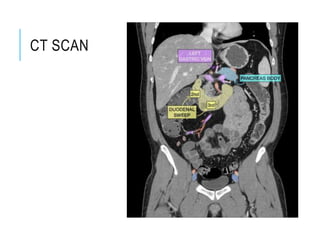

PANCREAS

The surface projection of

the head of the pancreas

lies within the duodenal

curve.

The neck lies in the

transpyloric plane, behind

the pylorus in the midline.

The body passes obliquely

up and to the left for

approximately 10 cm, its

left part lying a little above

the transpyloric plane.

The tail lies a little above

and to the left of the

intersection of the

transpyloric and left lateral

planes.